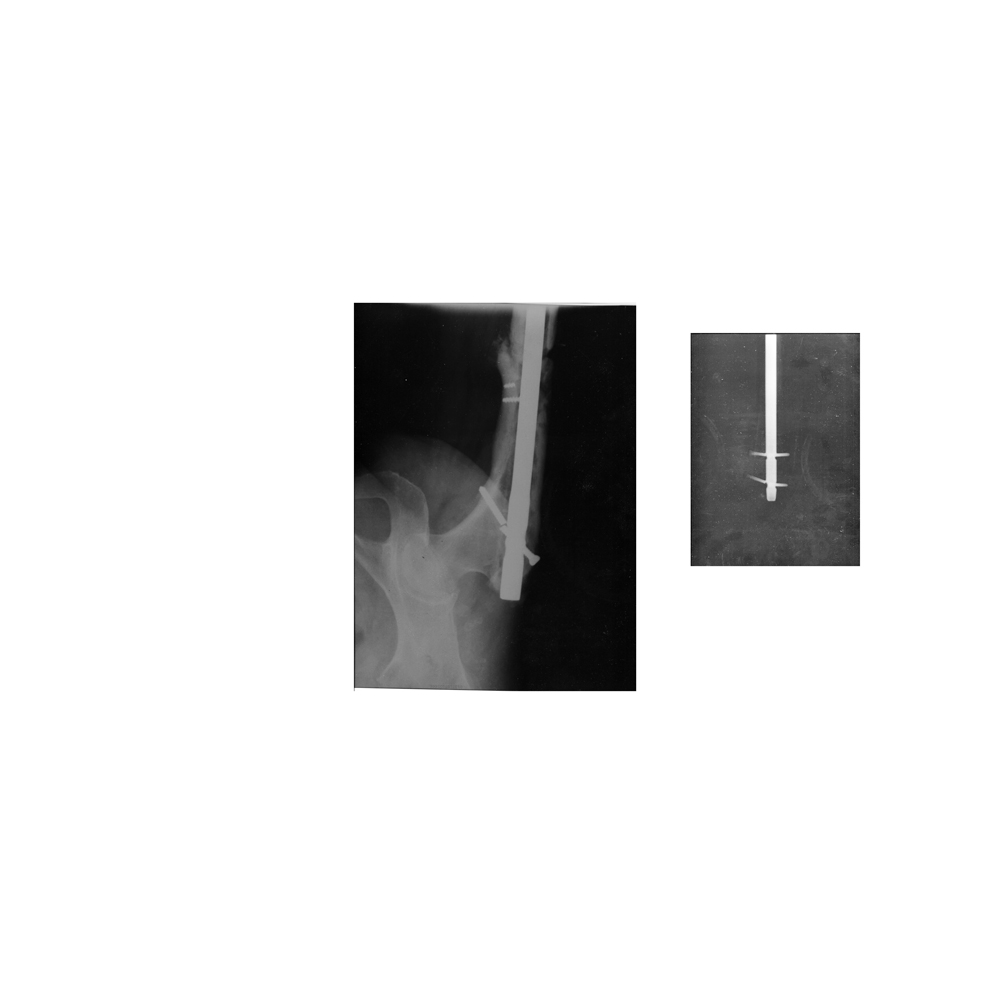

Здравствуйте! Насколько это серьезно?. Проведен остеосинтез бедренной кости гвоздем. Все блокирующие шурупы сломались. Что теперь меня ждет? Нужно ли менять шурупы ( дополнительная операция). Ужас в том, что это уже повторный остеосинтез ( перед этим сломался сам гвоздь).

Изначально был открытый перелом бедренной кости. Поставили пластину. Сняли поздно ( через 7 лет), половина сломанных шурупов осталась в кости. Перез пару недель после снятия сломалась кость. Потом начались истории, описанные выше.( на прилагаемых снимках поломанные шурупы и место перелома.Есть ли надежда, что он срастется ( перед этим был ложный сустав и поломанный гвоздь).

Ужаса никакого нет. Кроме качества снимков. Если есть несращение - надо делать какой-то реостесинтез. Что конкретно - надо увидеть хотя бы приемлемого качества снимки, Можно к нам очно появиться.